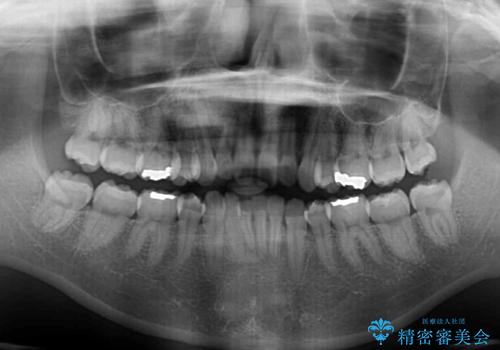

- 矯正治療の後戻りを気にして来院された患者様です。

後戻りは軽微であったので、インビザライン・ライトにより矯正治療を行うこととしました。

治療途中、妊娠・出産があり、1年近く治療が停滞しましたが、無事に終了することができました。